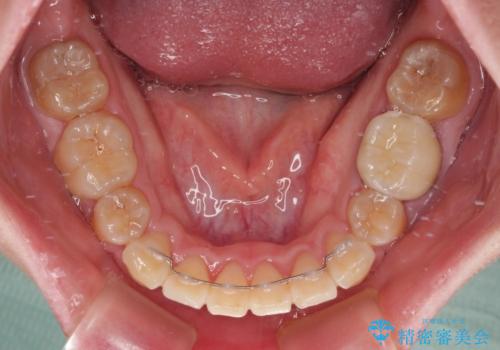

- クリアブラケット

- 2年4ヶ月

口元を積極的に引っ込めるために、上下左右の小臼歯計4本を抜歯することとしました。

4本の歯を抜歯したことで、飛び出していた口元が引っ込み、横顔が大きく改善されました。